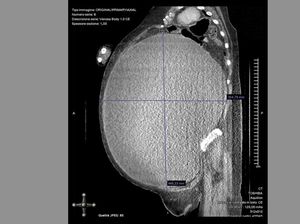

Kista Seberat 7,1 Kg Diangkat dari Tubuh Pasien RSUD Genteng Banyuwangi

Kista seberat 7,1 kilogram berhasil diangkat dari seorang pasien di RSUD Genteng, Banyuwangi. Pengangkatan kista seberat itu pertama kali terjadi di RS Genteng.